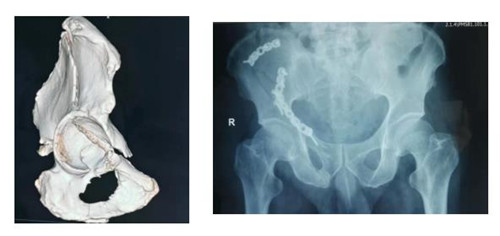

10月5日,江南在线体育骨三科收住一位不同寻常的患者。该患者自1.5米高处坠落,右髋部着地,致右髋部持续剧烈疼痛,不能行走站立,被他人救起送往就近医院。行X线、CT检查示:右髂骨、髋臼、耻骨升降支多发骨折。因手术难度较大,患者家属辗转渭南各医院,经多方打听胡洪波副主任医师在骨盆髋臼骨折治疗方面颇有经验,特前来我院。

接诊该病人后胡洪波副主任前往CT室对骨折移位情况进行分析、定位。经过详细询问病史、查体,结合检查结果,骨三科团队确定采用经腹旁外侧入路为患者进行手术。手术耗时短,出血少,骨折复位满意,固定可靠,患者和家属对治疗效果十分满意。

骨盆髋臼骨折腹旁外侧入路也是胡洪波副主任在骨盆髋臼骨折领域继stoppa入路之后带来了第二个新的手术入路。腹旁外侧入路是进行髋臼前柱骨折的新的手术入路方式,此入路临近血管、神经、腹膜等重要器管,所以临床中还未能广泛开展。但因为此入路具有切口小、创伤少、患者恢复快等巨大优点,近年来已逐渐应用于临床,为骨盆髋臼骨折患者的快速康复带来了福音。